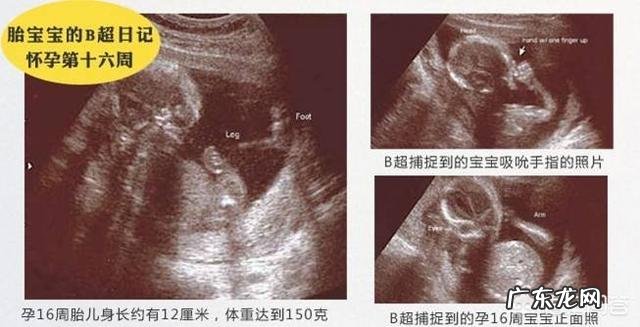

怀孕4个多月,通过B超可以清楚地看到胎宝宝的头部和躯干,其面部也清晰可见 。此时的胎宝宝大概身长12cm,体重约150克左右,可以说胎宝宝还非常的小,再加上充足的羊水,胎宝宝的姿势随时都有可能会发生变化 。

怀孕4个月的时候,胎宝宝的体重还只有150克,身长超过12厘米,大小像个鳄梨 。4个月的宝宝,在妈妈子宫里就像是宝宝在一个大大的游泳盆里,他可以自由自在的活动,踢踢腿、伸伸胳膊,甚至是翻个跟头 。在这个时候,一些敏感的妈妈已经能够感觉到轻微的胎动了,随着宝宝逐渐长大,胎动强度越来大,妈妈也会感觉到更加明显的胎动 。